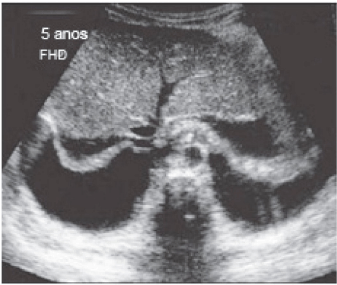

A febre do dengue hemorrágico (FDH) é uma arbovirose responsável por epidemias anuais no Brasil. Sua principal característica é o aumento da permeabilidade capilar, representada pela fuga de líquido e albumina para o espaço extravascular, levando a derrames cavitários e hemoconcentração com elevação do hematócrito, descrita como polisserosite, classificada em formas leves e graves, segundo critérios da Organização Mundial da Saúde. Embora os achados à ultrassonografia sejam inespecíficos, o método contribui para o diagnóstico precoce em pacientes com FHD e no diagnóstico diferencial de outras doenças febris.

Considerando as informações abaixo, assinale a alternativa correta quanto a principal hipótese diagnóstica da imagem ultrassonográfica apresentada.

Considerando as informações abaixo, assinale a alternativa correta quanto à principal hipótese diagnóstica da imagem ultrassonográfica apresentada.